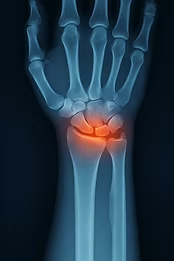

Scapholunate dissociation (Scapholunate Dissociation, SLD) is the most common and clinically important ligament injury in the wrist. It occurs due to injury to the scapholunate ligament (SLL) and leads to instability between the scaphoid and lunate. Radiologically, this appears as an abnormally large gap between the bones – often referred to as the "Terry Thomas sign"¹–³.

PA radiograph: scapholunate gap > 3 mm (= pathological)

SL gap > 3 mm (Terry Thomas sign)